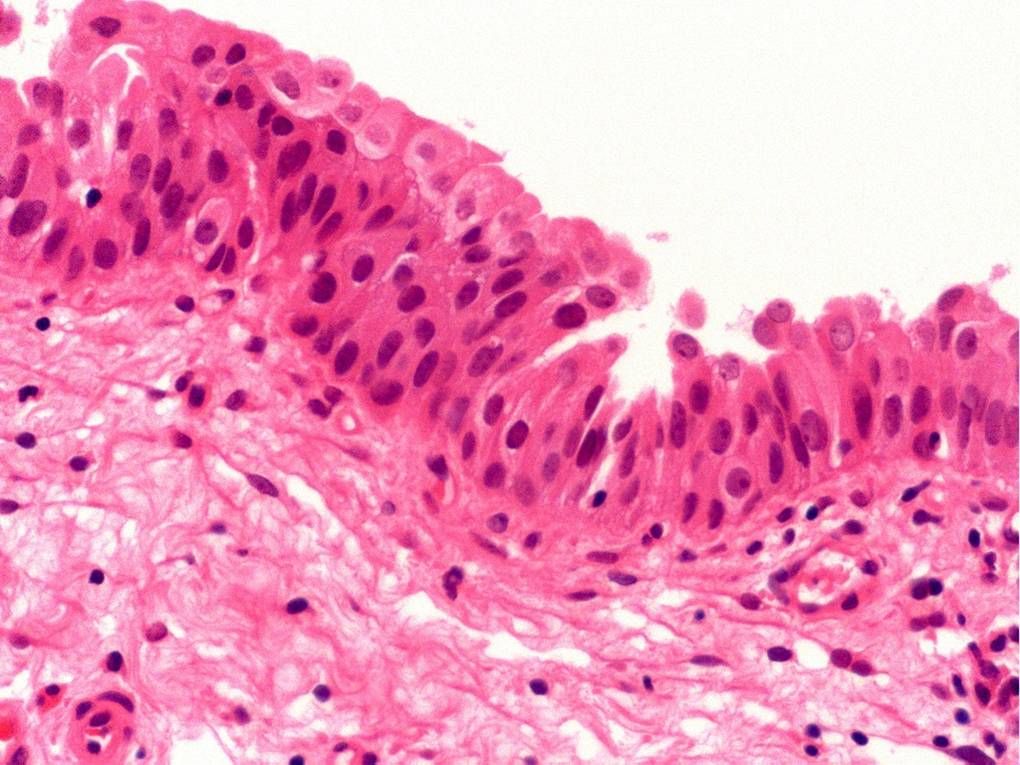

Bladder Flat Lesions

Case ID: 80